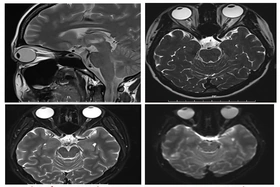

baophutho.vn Trung tâm Y tế khu vực Cẩm Khê những ngày qua đã tiếp nhận nhiều trường hợp đến khám và điều trị với các triệu chứng như méo miệng, mắt nhắm...